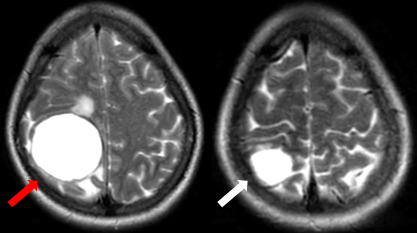

Sau 8 tháng điều trị, bệnh nhân không còn ghi nhận những cơn co giật, bệnh nhân không khó thở, không đau ngực. Trên phim chụp cộng hưởng từ não, kích thước khối u giảm đáng kể là một minh chứng cho sự đáp ứng tốt với thuốc của bệnh nhân. Phim chụp cắt lớp vi tính cũng ghi nhận kích thước khối u giảm hơn so với phim chụp cũ.

Hình 3. Hình ảnh phim chụp cộng hưởng từ não ngày 28 tháng 6 năm 2023 (mũi tên trắng) so với ngày 27 tháng 10 năm 2022 (mũi tên đỏ), kích thước khối u giảm so với phim chụp cũ.

Hình 4. Hình ảnh phim chụp cắt lớp vi tính lồng ngực cho thấy kích thước khối u ngày 28 tháng 6 năm 2023 (mũi tên trắng) giảm hơn so với phim chụp ngày 27 tháng 10 năm 2022 (mũi tên đỏ).

Sau đó, bệnh nhân tiếp tục duy trì điều trị với osimertinib đến thời điểm đánh giá lại tháng 9 năm 2024, sau gần 2 năm điều trị, bệnh nhân vẫn đáp ứng rất tốt, không đau ngực, không khó thở, chỉ điểm khối u CEA và Cyfra 21-1 duy trì ở mức bình thường. Hình ảnh u phổi trên phim cắt lớp vi tính không thay đổi nhiều song trên phim cộng hưởng từ, kích thước khối u giảm đáng kể.

Hình 5: Hình ảnh khối u não trên phim cộng hưởng từ qua các mốc thời gian 10/2022, 6/2023, 6/2024 và 9/2024.